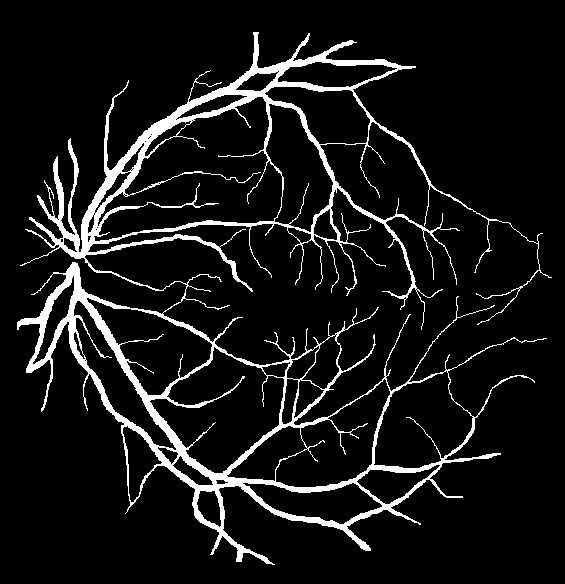

Refer to caption

(a) Ground truth binary mask

(b) Thick vessels binary mask

(c) Thin vessels binary mask

Figure 4: Segregation of ground truth of sample DRIVE image.

After Level-I balancing, the network model is still biased towards the prediction of thick vessel pixels, leaving many thin vessel pixels unidentified. This is because the number of thick vessel’s pixels exceeds those of thin vessel’s pixels. Thus, there is a need to create a balance between the distribution of thick and thin vessel pixels in the training set, termed intra-class balancing. This can be considered another level of balancing on top of Level-I balancing, hence the term Level-II balancing. The balancing obtained from Level-I is further refined by giving an equivalent representation to thick vessel pixels and thin vessel pixels in the training set. The categorization of thick and thin vessel patches requires the segregation of ground truth binary images based on thick and thin vessel pixels. The thick vessels pixels mask is acquired through morphological opening [44] operation, while the thin vessels pixels mask is obtained by subtracting the thick vessel mask from the original ground truth mask. Figure 4 shows the ground truth image of a sample DRIVE image along with the corresponding thick and thin vessel mask images.